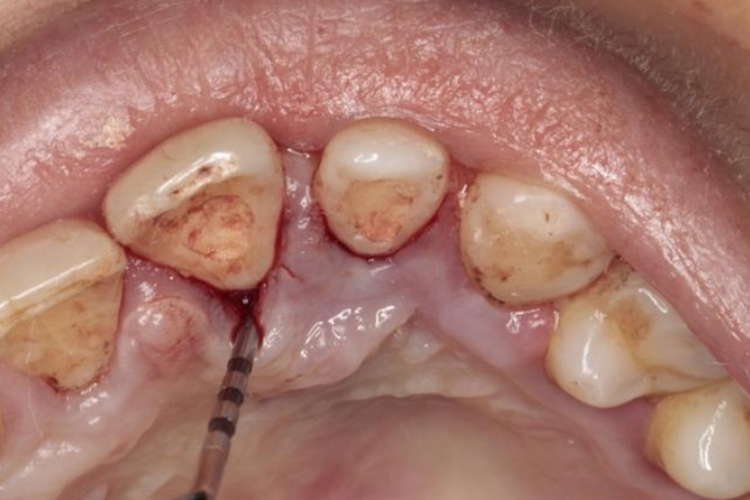

轻度牙周袋是龈沟病理性加深后在牙根与牙龈之间形成的开口于冠方的盲袋。轻度牙周袋内容物成分复杂,含有菌斑、软垢、龈沟液、食物残渣等,具有较大的毒性。袋壁软组织可受根面龈下牙石的机械刺激和炎性反应的多重影响,从而引起袋内出血。

轻度牙周袋需要进行基础性牙周治疗,如洁治、刮治、咬合调整等处理。如果复诊时经评估后仍有深牙周袋时,也可考虑进行牙周手术治疗,消除深部感染和炎症,并纠正解剖形态,促进牙周组织的修复和再生。